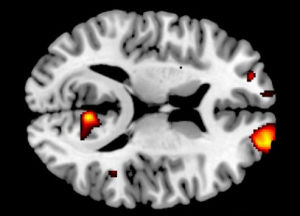

研究發現腦中灰質較多的人更加無私2012年9月,研究人員稱大腦內頂葉和顳葉結合處有更多灰質的人更無私。這項研究首次表明了大腦解剖、大腦活動和利他行為之間存在著聯繫。

以往的研究表明,大腦的某些區域—頂葉和顳葉交匯的地方與一個人換位思考的能力有關。利他主義者在了解他人的想法和感受的能力更強。因此,研究人員認為,大腦中這部分的個體差異可能與利他行為的差異有關。蘇黎世大學經濟學系博士後研究員YosukeMorishima說:“表現更無私的人在大腦的頂葉和顳葉結合處有更多的灰質。”